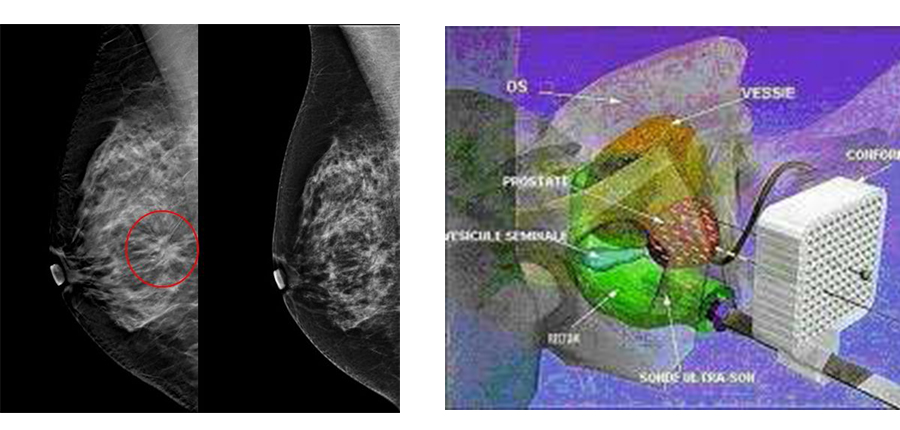

Dans le cadre de la formation continue post-universitaire, le Centre 'Oncologie AL AZHAR de Rabat, organise une Table Ronde le 18 Avril 2017 à l'Amphitrite Skhirat sur les actualités dans les Cancers du sein métastatiques en 2017,les pièges de la mammographie,la curiethérapie dans le cancer de la prostate ainsi que l'étude de Cas cliniques pratiques.